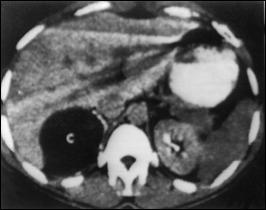

Fig.19. Adenom suprarenalian stâng secretant de aldosteron (sindrom Conn) - aspect TC. |